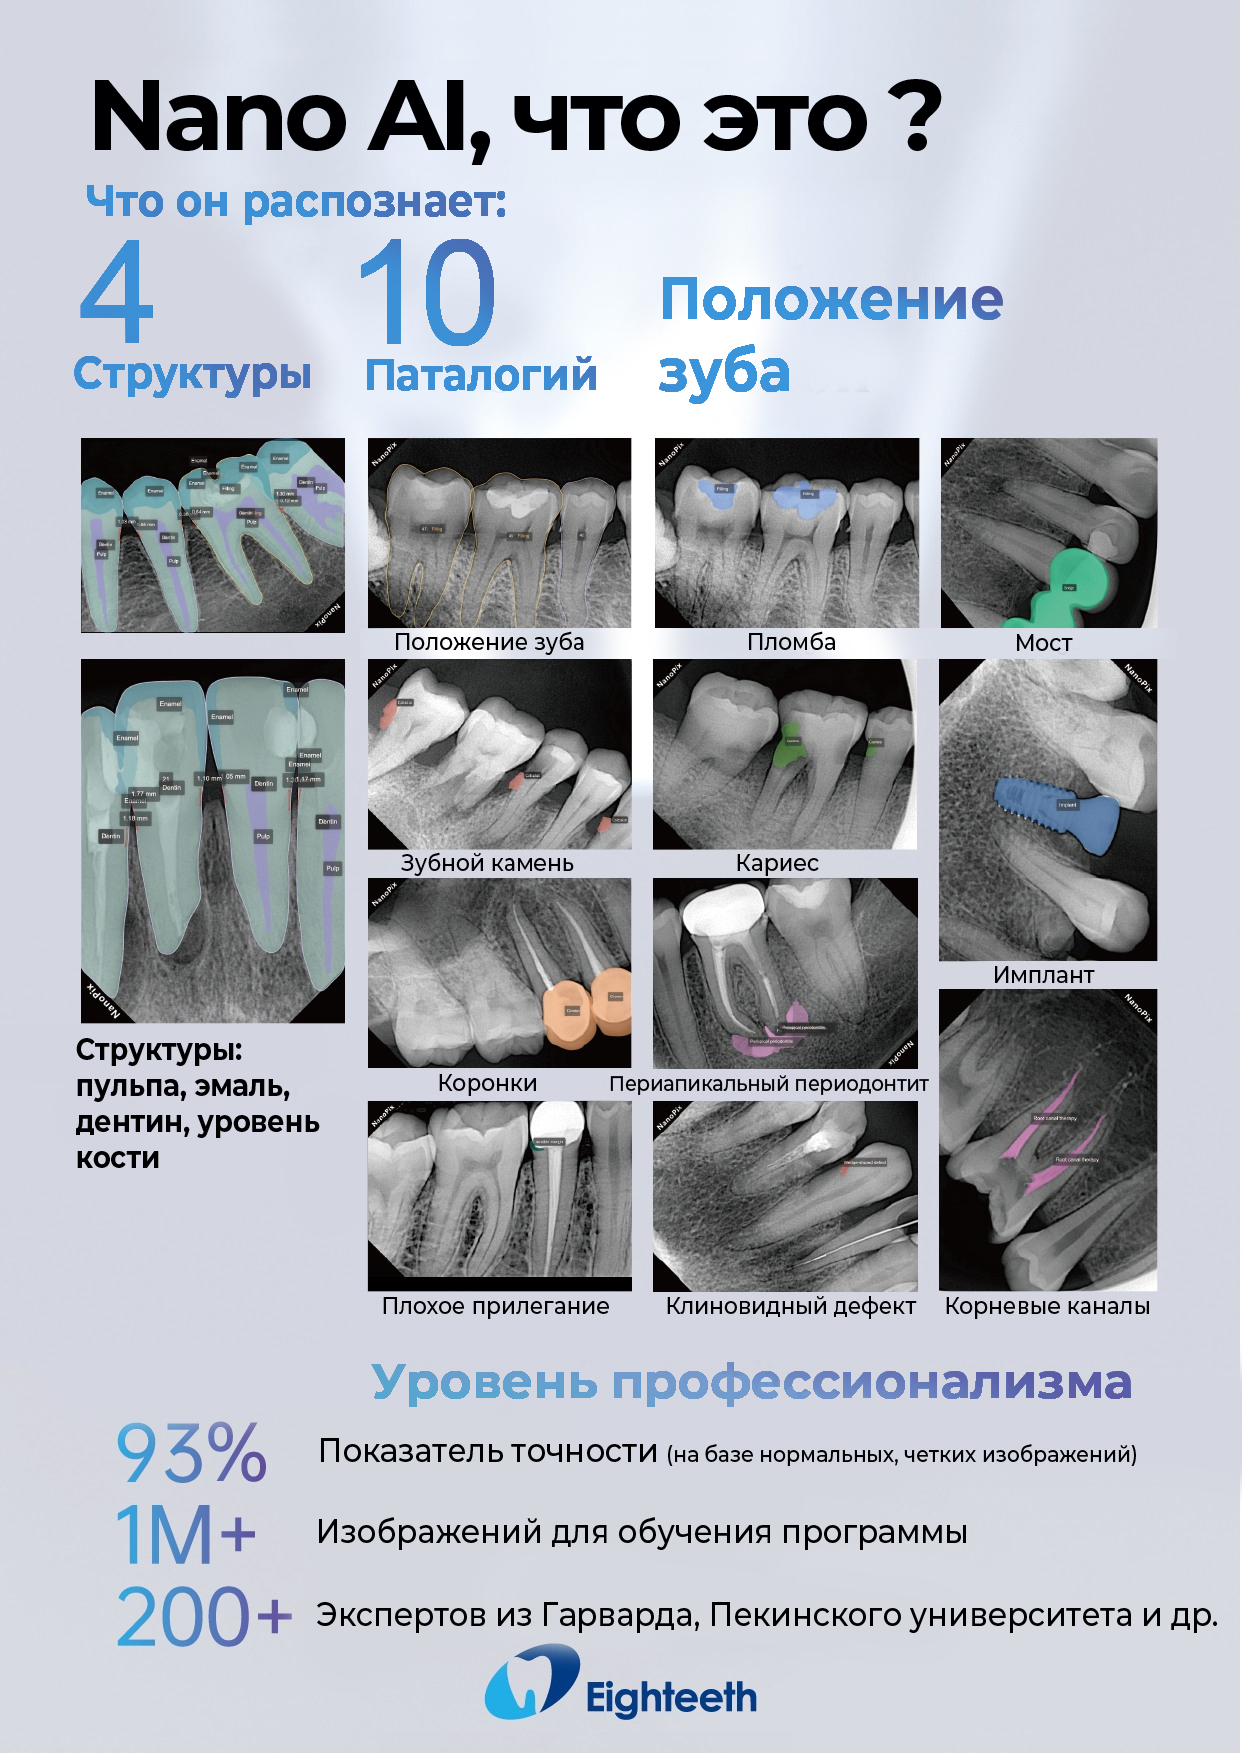

Прибор оснащён высокочувствительным сенсором, с помощью которого устройство фиксирует и передаёт изображение в цифровом виде на компьютер. Принцип работы заключается в следующем: цифровой радиовизиограф размещается в ротовой полости пациента за зубами. С щёчной стороны дентальный рентгеновский аппарат выпускает в направлении радиовизиографа рентгеновские лучи. Лучи, проходя через ткани зуба, фиксируются на радиовизиографе, и полученная информация отображается на экране компьютера. Уникальная технология искусственного интеллекта Nano AI распознаёт зубные патологии, выделяя их цветом и предлагая возможные способы лечения.